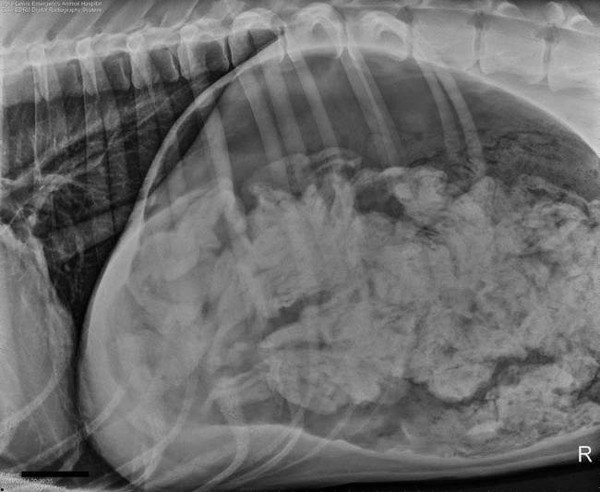

Theo bệnh viện thú y cho biết, Kết quả chụp X-quang cho thấy, trong dạ dày của chú chó Great Dane có một số lượng dị vật. Các bác sĩ nghi ngờ chú chó này đã ăn tất của chủ nhân khi đói miệng. Phải mất tới hơn 2 tiếng đồng hồ phẫu thuật, họ mới gắp bỏ được tổng cộng 43 chiếc tất ra khỏi dạ dày của con vật. Ngoài ra, các bác sĩ còn tìm thấy 1 vật có hình dáng như gót giày cũng bị nó nuốt phải.

Sau khi phát hiện chú chó 3 tuổi giống Great Dane có biểu hiện nôn ọe và rên rỉ không ngừng trong vài tuần, chủ nhân của chú chó đã đưa nó tới một Trạm Cấp cứu Thú y DoveLewis, thành phố Portland, bang Oregon, Mỹ để khám bệnh. Tại đây, các bác sĩ đã tìm thấy hàng chục chiếc tất đang nằm gọn trong dạ dày của chú chó này.